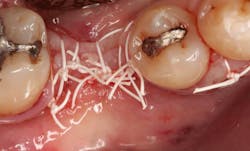

In this case, I placed an autogenous fibrin clot, which was isolated from the fractionated blood draw, over the Ossix Plus membrane and sutured, without obtaining primary closure, using a CV-5 Gore-Tex (W.L. Gore & Associates Inc.). This technique is designed to help facilitate the formation of a blood clot over the Ossix Plus membrane. It can be used with the addition of a collagen plug over the membrane, or you can just suture and allow a natural clot to form.

The patient was placed on Augmentin for 10 days, given anti-inflammatory pain medication (flurbiprofen, 100 mg, bid), and instructed to rinse with chlorhexidine gluconate 0.12% rinse for one minute in the morning and one minute prior to bedtime. The patient was instructed not to eat or drink anything for 20 minutes after rinsing with chlorhexidine gluconate 0.12%. The sutures were left in place for two weeks, and the patient was instructed not to brush the teeth adjacent to the No. 20 space during that time.